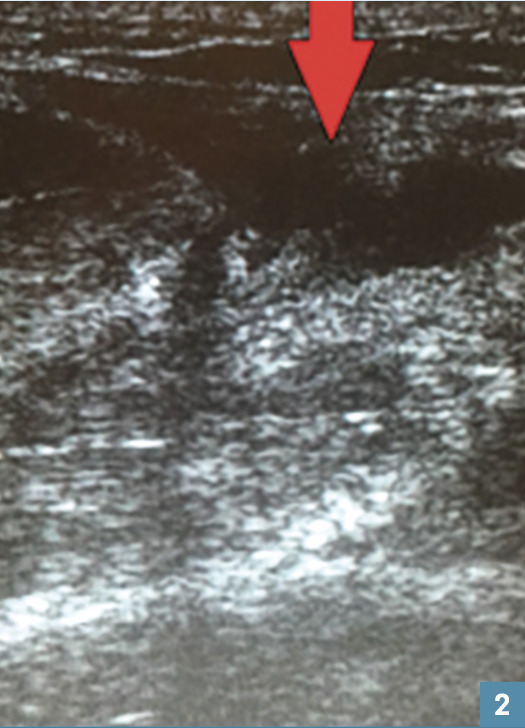

L’échographie montre une zone hétérogène hypo-échogène (grand axe de 4 cm) « coupant » le muscle (fig. 2 ).

L’échographie montre une zone hétérogène hypo-échogène (grand axe de 4 cm) « coupant » le muscle (

Une échographie est réalisée systématiquement en première intention pour affirmer le diagnostic. En cas de rupture, elle révèle 2 régions hyperéchogènes séparées par une vaste poche séro-hématique. L’IRM n’a de place qu’en deuxième ligne et sur avis du spécialiste.